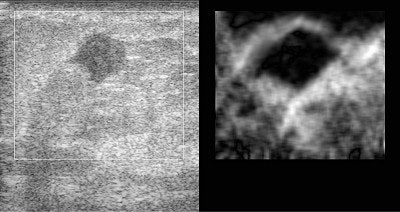

| The above image has some of the features typical of breast cancer: the tumor is hypoechoic (dark compared to its surroundings), and has an irregular boundary. The palpation image (an image of relative mechanical strain) of this lesion shows that the lesion is stiffer than its surroundings (dark compared to its background), and appears larger in the palpation image than in the B-mode image. |